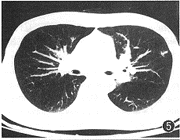

图5 AIDS合并肺结核,左上肺小斑片状影像

1.肺内斑片状影像:1例(图5)。